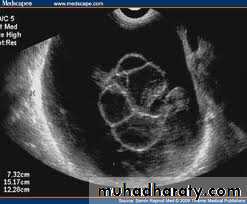

Images from women with differing expressions of the four major subtypes of the metabolic syndrome associated with polycystic ovary syndrome (A–D). The images exhibit quite differing ultrasonographic appearances in the size and distribution of follicles within PCOS ovaries. A recent corpus luteum is clearly visible in the ovary in panel (D).

• POLYCYSTIC OVARY SYNDROME

Images from women with differing expressions of the four major subtypes of the metabolic syndrome associated with polycystic ovary syndrome (A–D). The images exhibit quite differing ultrasonographic appearances in the size and distribution of follicles within PCOS ovaries. A recent corpus luteum is clearly visible in the ovary in panel (D).• POLYCYSTIC OVARY SYNDROME

Images from women with differing expressions of the four major subtypes of the metabolic syndrome associated with polycystic ovary syndrome (A–D). The images exhibit quite differing ultrasonographic appearances in the size and distribution of follicles within PCOS ovaries. A recent corpus luteum is clearly visible in the ovary in panel (D).The Oviduct (Fallopian Tube)